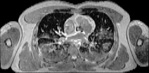

Visible Human male: Sectio transversalis 1424

CT

NMR

Pd                          / T2 \                         T1